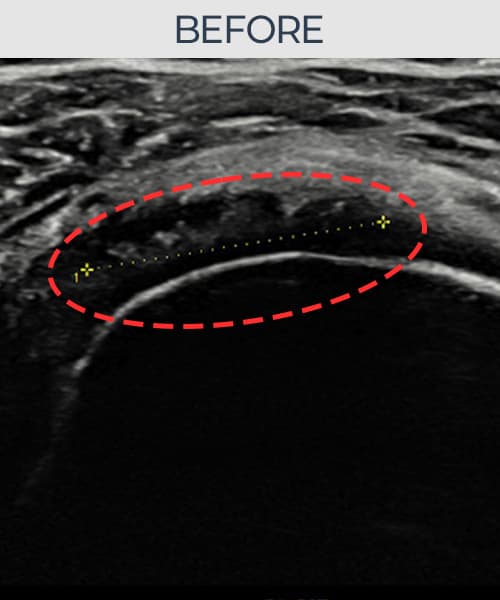

시술 전 초음파 측정 결과 파열 크기는 11mm × 6mm (힘줄 두께의 약 58% 결손)로 확인되었습니다. 시술 전 초음파에서 회전근개의 연속성 단절과 부착부 인대 두께의 현저한 감소가 확인되었습니다. 시술 후 초음파에서는 봉합된 인대의 연속성이 회복되고 부착부 두께가 정상 범위로 증가하였으며, 내부 에코 패턴도 균질하게 개선되었습니다.

50대 초반 남성 환자분으로, 물류 창고에서 무거운 물건을 반복적으로 들어올리는 작업을 10년 이상 해오신 분이었습니다. 타 기관에서 충격파 치료를 3개월 받았으나 효과가 없어 내원하셨고, 정밀 초음파 검사에서 회전근개 부분파열과 인대 손상이 복합적으로 확인되었습니다. 단순 주사 치료나 물리치료로는 구조적 문제를 해결하기 어렵다고 판단하여 초음파 유도 하 축소봉합술을 시행하였습니다. 시술 당일 귀가 후 보조기를 착용하였으며, 4주 후부터 단계적 재활 운동을 시작하였습니다. 시술 후 6주 시점에 초음파 재검사에서 봉합 상태가 양호함을 확인하였고, 18개월 최종 경과 관찰에서 인대 두께 회복과 구조적 안정화가 확인되어 직장 복귀에 성공하셨습니다.